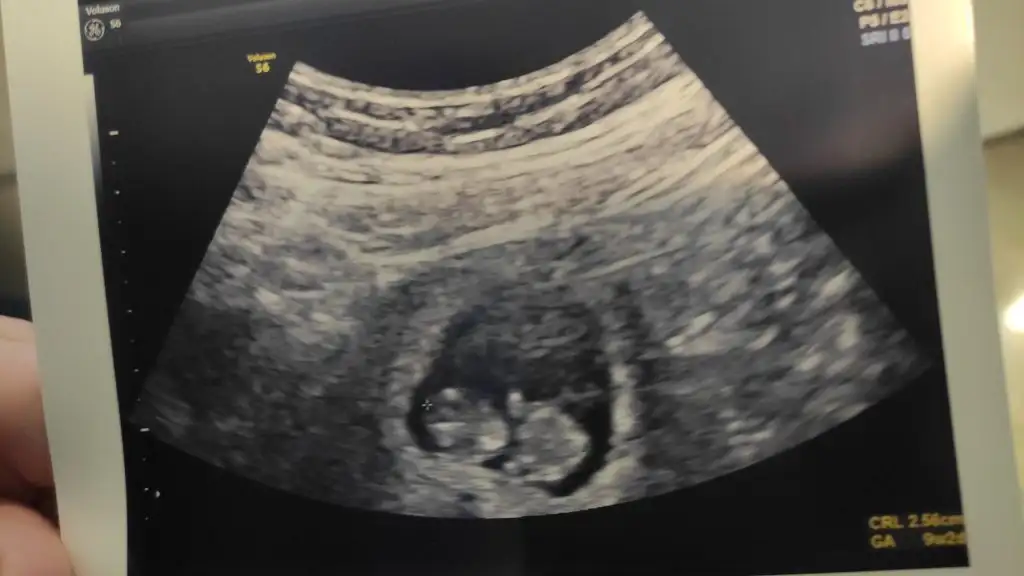

Canım benim bende yazicaktim sabahtan beri fırsatım olmadı bı türlüBende dün doktora gittim çok şükür hersey yolunda...Dün tam 9 haftalıkti doktor 9 hafta 2 gün ölçtü ama bu 1-2 gün oynayabilir önemli değil dedi...

Çok korkarak gittim genelde bu haftalarda kaybettiğimiz için doktor gösterince ağlamaya başladım

12. Haftada gelirsin dedi ikili test için vs ...

Maşallah maşallahCanım benim bende yazicaktim sabahtan beri fırsatım olmadı bı türlüBende dün doktora gittim çok şükür hersey yolunda...Dün tam 9 haftalıkti doktor 9 hafta 2 gün ölçtü ama bu 1-2 gün oynayabilir önemli değil dedi...

Rabbim inşallah sağlıkla hayırla herkese tüm isteyenlere nasıp etsinMaşallah maşallaho üç beş günlük oynamalar belirli bir güne kadar normal sayilirmis hiç merak etme bukez birşey olmaz inşallah içini ferah tut kıyamam git git aklında kalmasın tabi